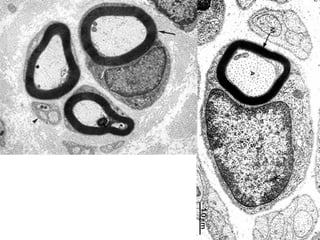

• #13 Electron microscope section, peripheral nerve. How many axons are myelinated? Perhaps about 7? Are the rest UN-myelinated? YES

• #14 Please differentiate between microtubules (small circles) and neurofilaments (dots). Find the schwann cell nucleus, find an UNmyelinated axon, find a mitochondrion.